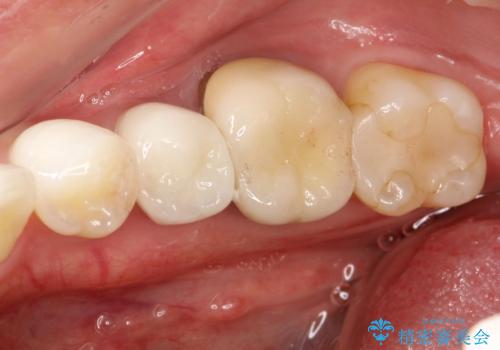

右下5の神経は失活してしまっているため、根管治療の必要性を説明の上、根管治療をした後セラミッククラウンを入れていくこととなりました。

患者さんに確認したところ、今回の右下5は痛みを覚えた記憶はなかったそうです。

神経が死んでしまうときは、多くは痛みを伴うことが多いですが、今回のように気づいたら死んでしまっているというケースもあります。その場合、なかなか自覚症状なく病気が進行してしまうこともあるため、定期的にメンテナンス、レントゲンによる確認をすることが大切です。